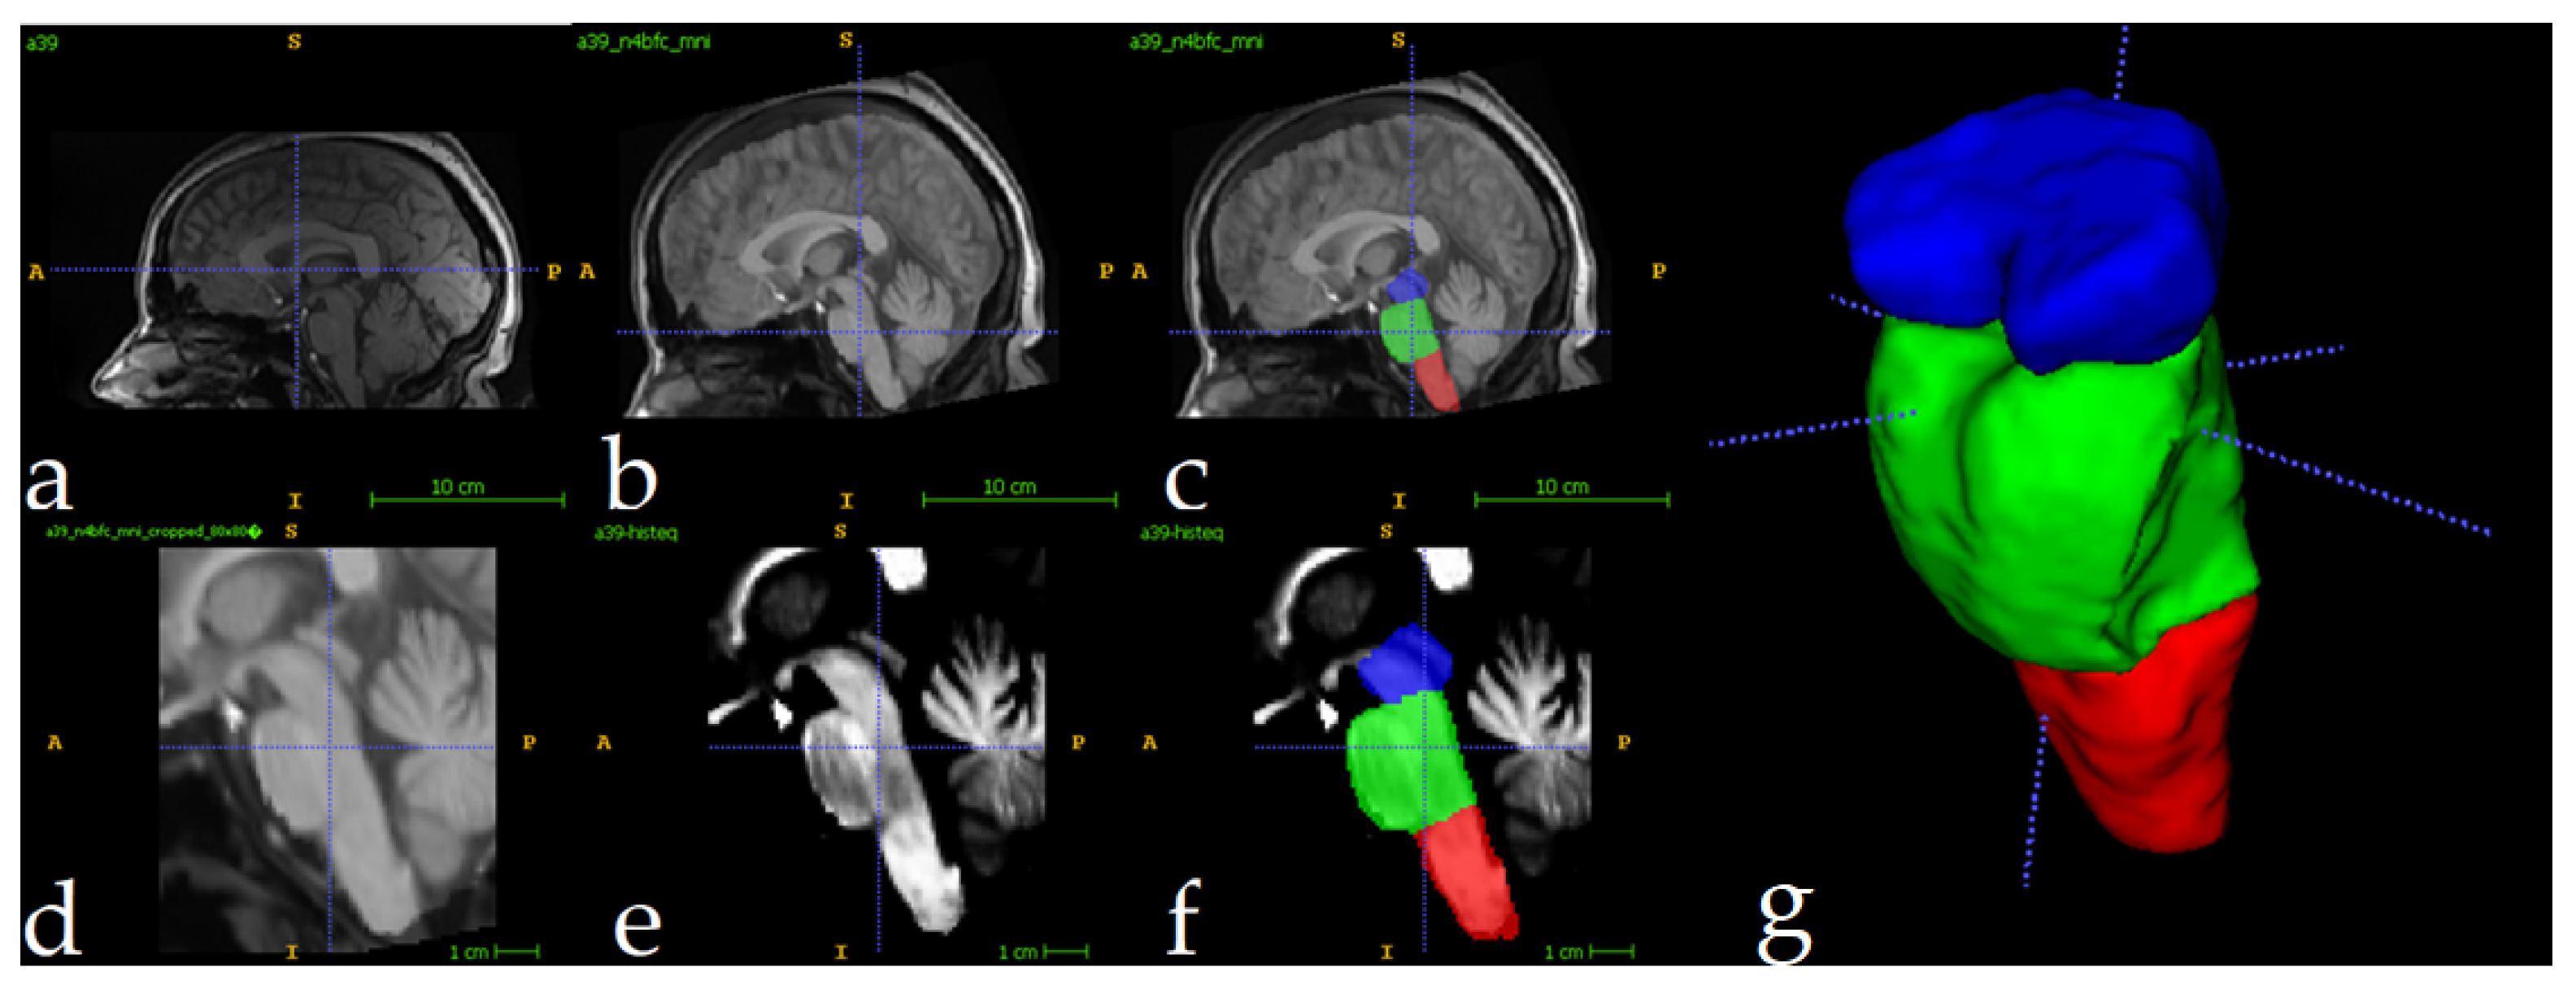

- Superior Segmentation Performance: The proposed modified U-Net architecture (with attention-enhanced skip connections and inception modules) significantly outperforms three comparative approaches in brainstem parcellation, achieving higher Dice scores across all substructures (medulla, pons, mesencephalon) and the whole brainstem.

- Volume Differences Across Groups: Automated segmentation reveals distinct volumetric patterns, with controls exhibiting larger volumes (whole brainstem: 1.62) compared to preclinical (1.49) and patient groups (1.12), suggesting potential atrophy linked to disease progression.

- Clinical Utility: The method’s accuracy and robustness support its potential for precise brainstem assessment in neurodegenerative disorders, enabling earlier detection of structural changes (e.g., reduced medulla volume in patients: 0.26 vs. 0.31 in controls).

| Mesencephalon | 0.96±0.022 | 0.91±0.023 | 0.93±0.019 | 0.89±0.031 |

| Pons | 0.96±0.015 | 0.93±0.016 | 0.94±0.013 | 0.91±0.029 |

| Medulla | 0.95±0.021 | 0.91±0.022 | 0.92±0.021 | 0.91±0.023 |

| Full brainstem | 0.96±0.008 | 0.94±0.008 | 0.95±0.007 | 0.93±0.013 |